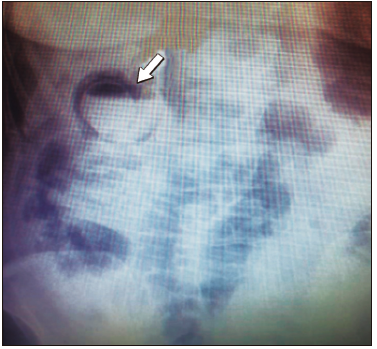

Como primer estudio se realizó una radiografía directa de abdomen. (Figura 3) Se solicitó una ecografía abdominal y una TC de abdomen de urgencia donde se informó la presencia de aire en la pared e interior de la vesícula.

Figura 3. Radiografía directa de abdomen. Se observa imagen radiolúcida (flecha

blanca) en el hipocondrio derecho en topografía de la vesícula biliar relacionada, posiblemente, con

enfisema parietal de dicho órgano, asociado a nivel hidroaéreo. Podría tratarse de un cuadro de CE